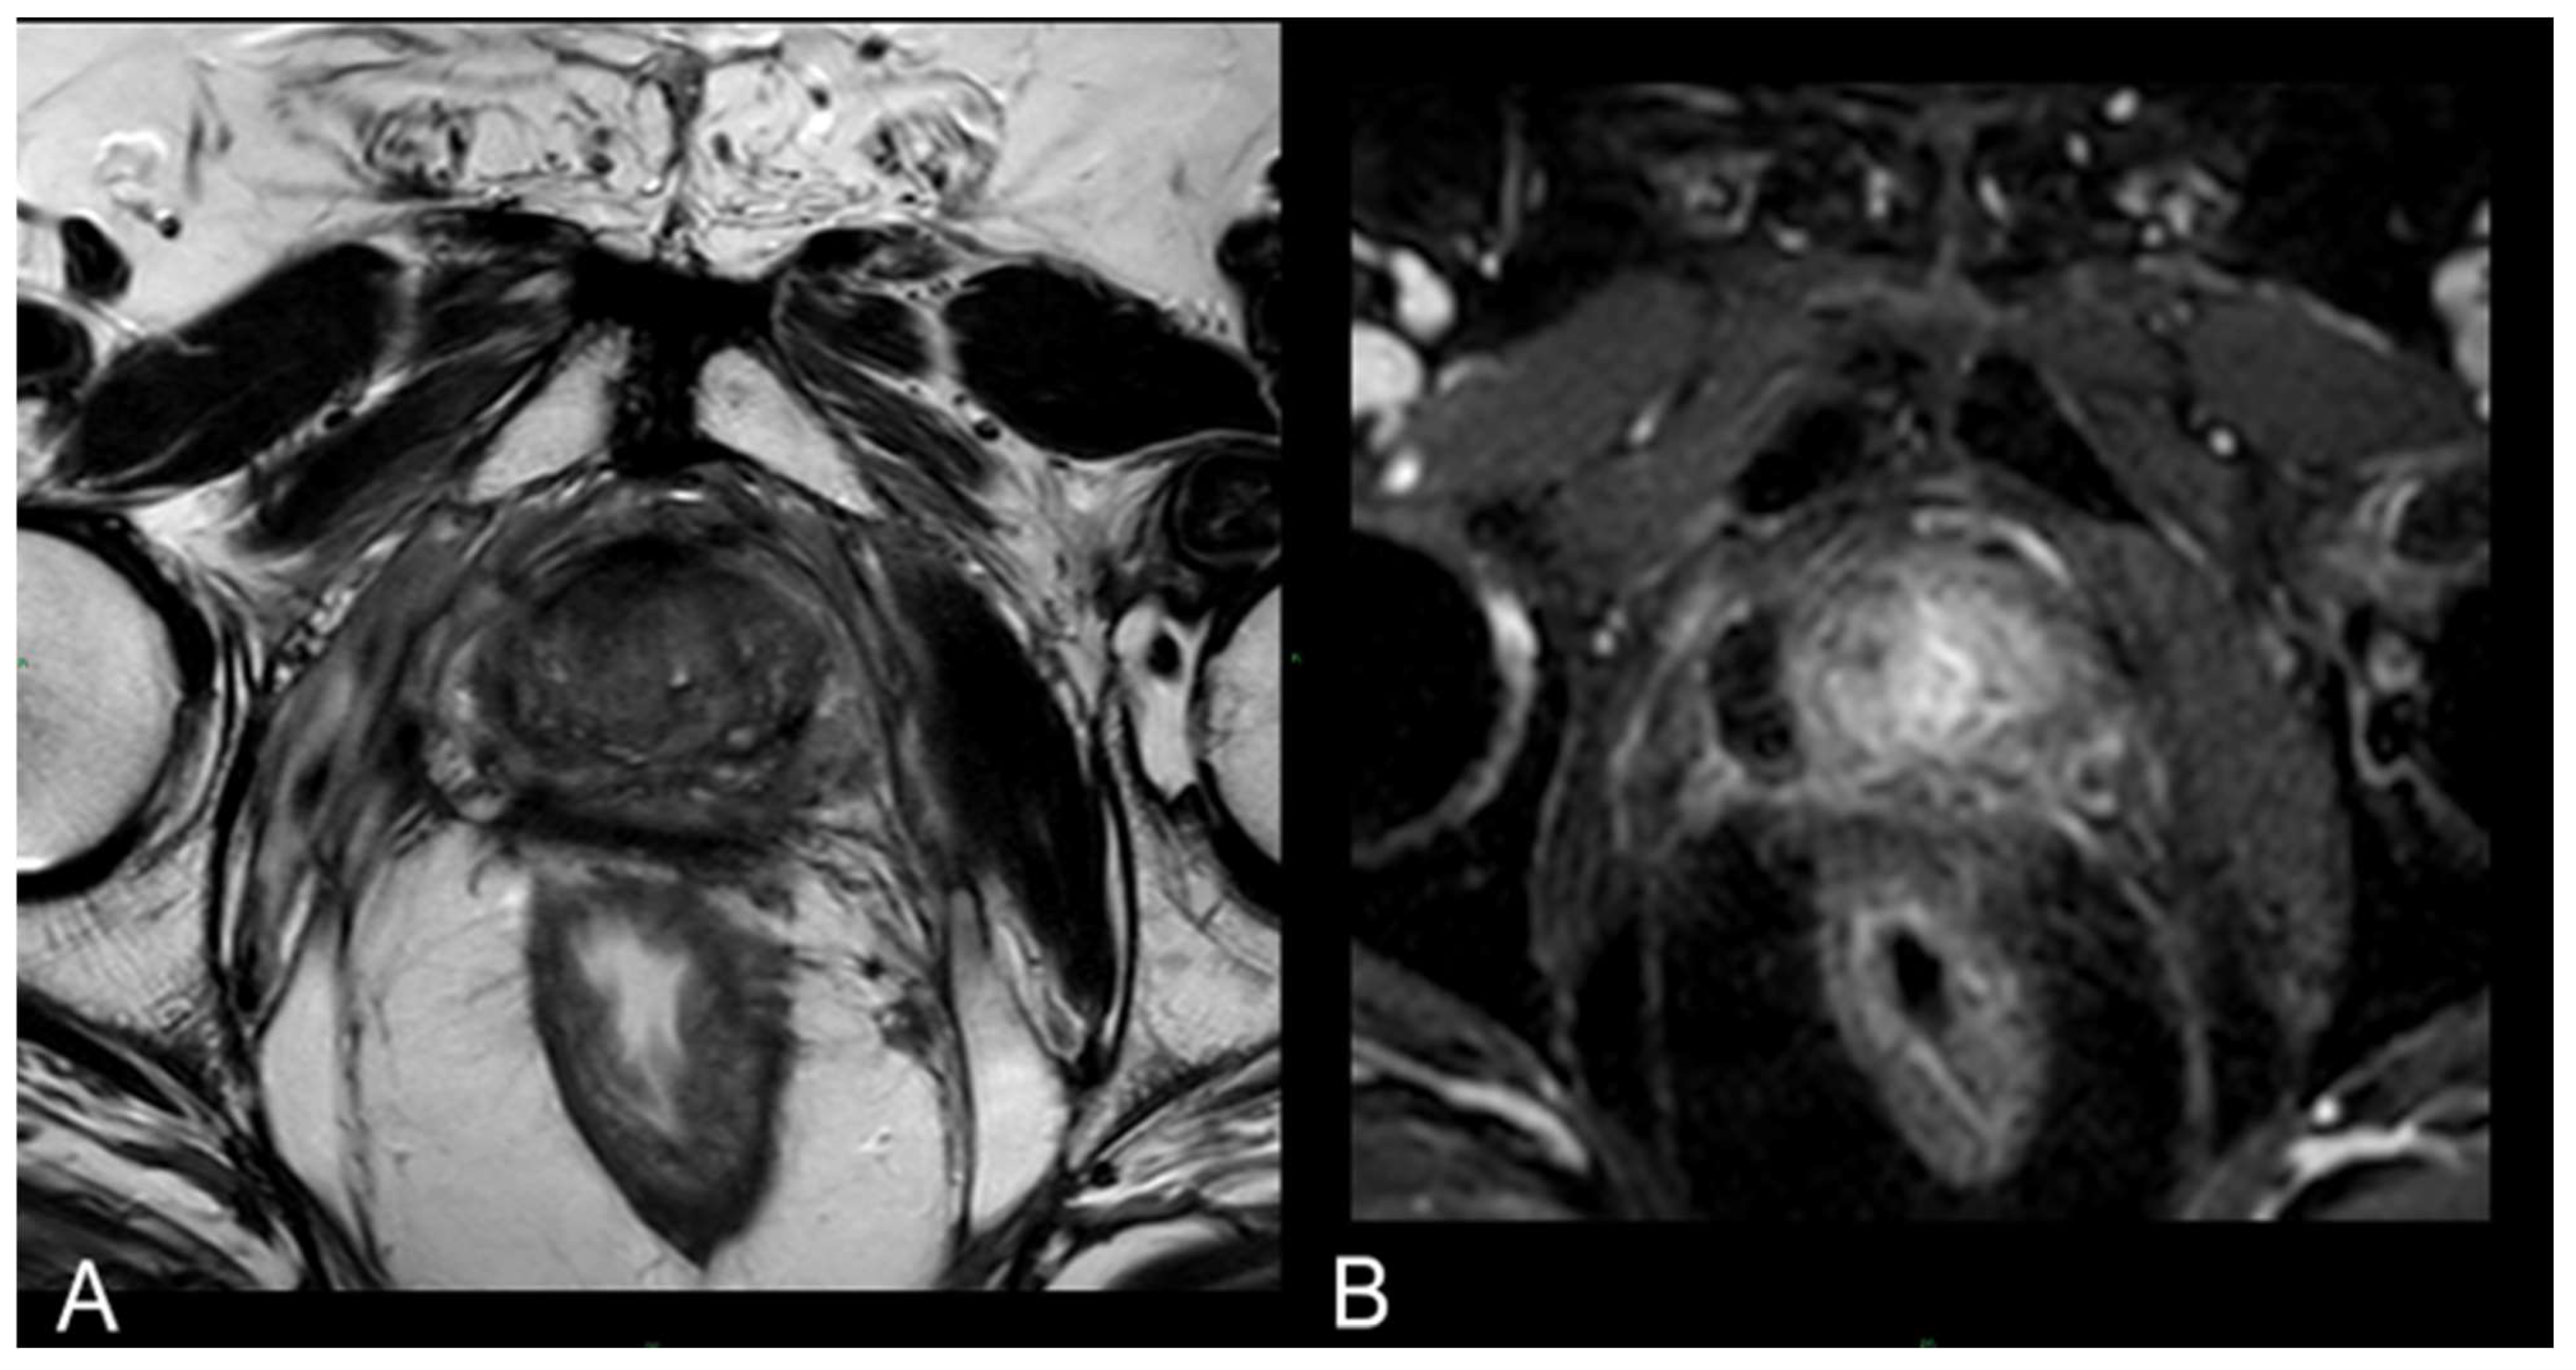

3.2. mpMRI-Derived Results